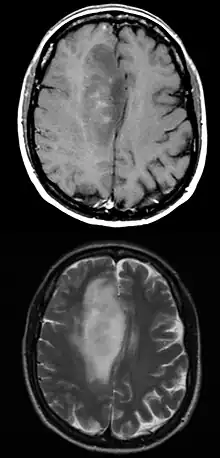

.jpg.webp)

When viewed with MRI, glioblastomas often appear as ring-enhancing lesions. The appearance is not specific, however, as other lesions such as abscess, metastasis, tumefactive multiple sclerosis, and other entities may have a similar appearance.[42] Definitive diagnosis of a suspected GBM on CT or MRI requires a stereotactic biopsy or a craniotomy with tumor resection and pathologic confirmation. Because the tumor grade is based upon the most malignant portion of the tumor, biopsy or subtotal tumor resection can result in undergrading of the lesion. Imaging of tumor blood flow using perfusion MRI and measuring tumor metabolite concentration with MR spectroscopy may add diagnostic value to standard MRI in select cases by showing increased relative cerebral blood volume and increased choline peak, respectively, but pathology remains the gold standard for diagnosis and molecular characterization.